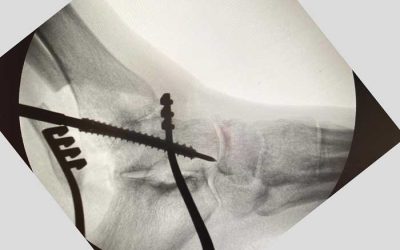

Osteocondritis medial del astrágalo en el tobillo: qué es

Feb 22, 2025

Lo que debes saber sobre el diagnóstico, tratamiento y recuperación de la osteocondritis medial del astrágalo La...